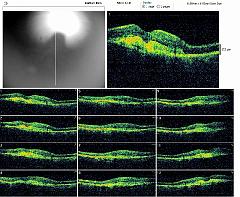

REPERTOIRES ANGIOGRAPHIES

Chaque dossier correspond à un cas dans lequel peuvent se trouver plusieurs examens à des dates différentes.

Path: /3101-20091224-01/18-08-2010/thumbs